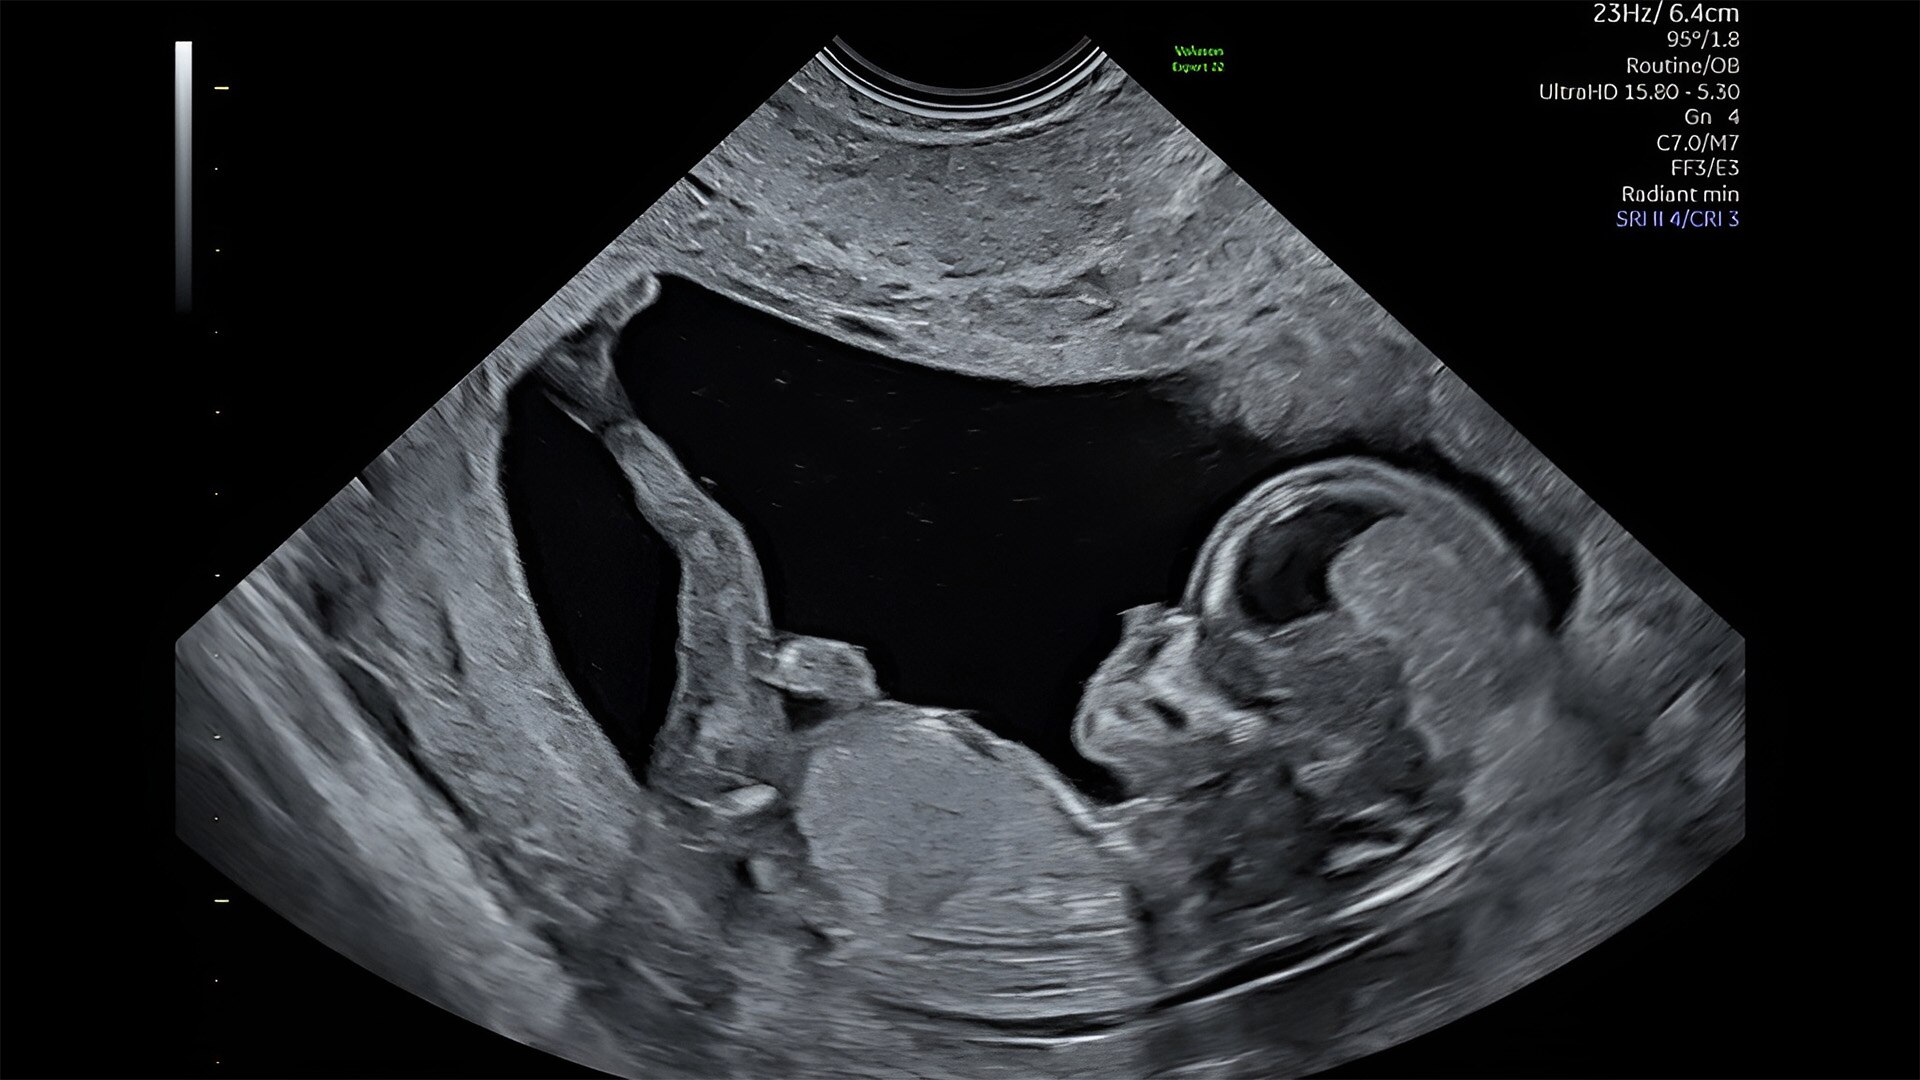

First trimester exams

Perform detailed exams with high-resolution for early insights to fetal health